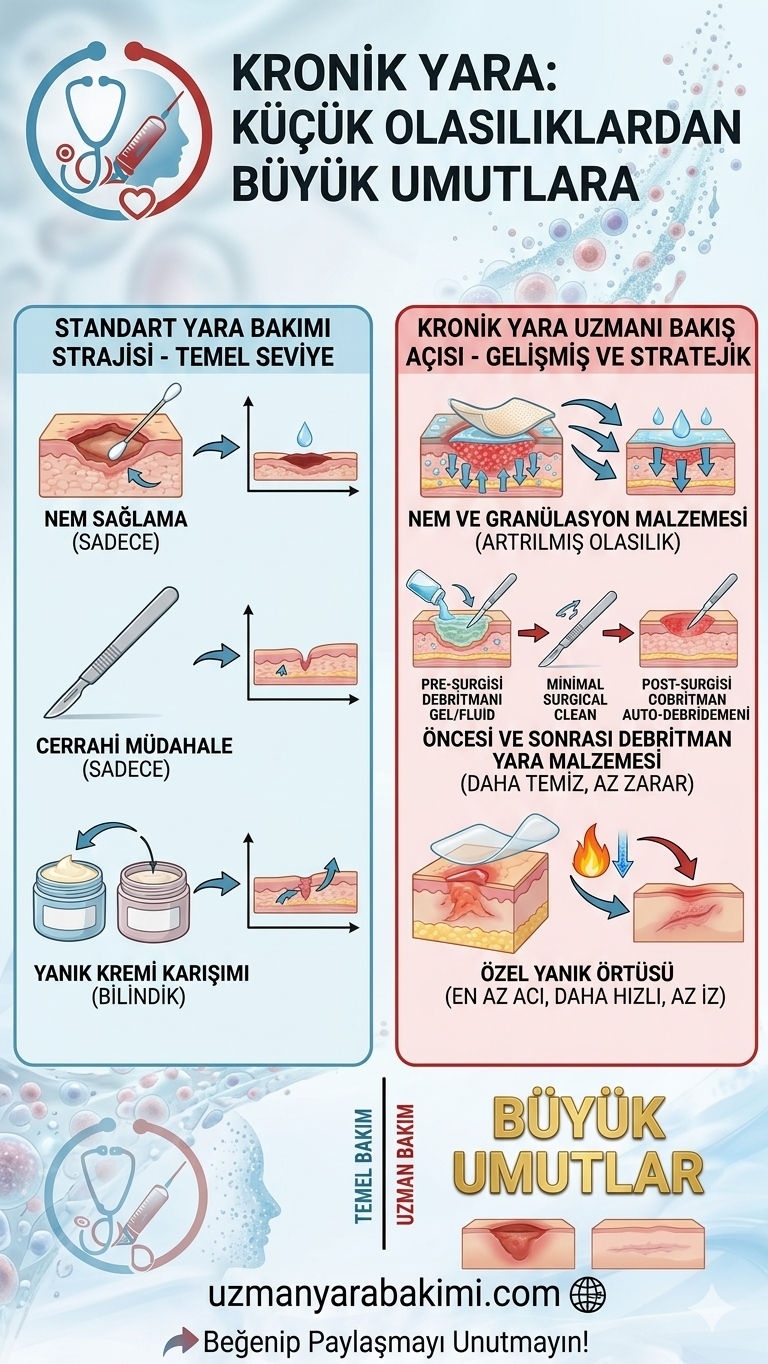

Yara bakımı, yüzlerce eğitimle temeli atılan ancak ancak sahanın en zorlu alanlarında "pişerek" mükemmelleşen bir disiplindir. Profesyonel hemşirelik ve uzman yara bakımı yetkinliği, akademik başarıyı saha tecrübesiyle taçlandırmayı gerektirir.

Vizyonumuz; yara bakımını sadece teknik bir müdahale olarak değil, klinik tecrübe, ileri teknoloji ve insan odaklı yaklaşımın mükemmel uyumu olarak yeniden tanımlamaktır.